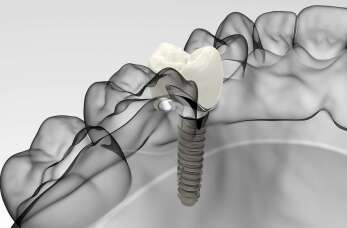

Implantologia stomatologiczna to dziedzina medycyny zajmująca się wprowadzaniem implantów dentystycznych, które zastępują brakujące zęby. Proces ten rozpoczyna się od diagnostyki, pozwalającej ocenić...